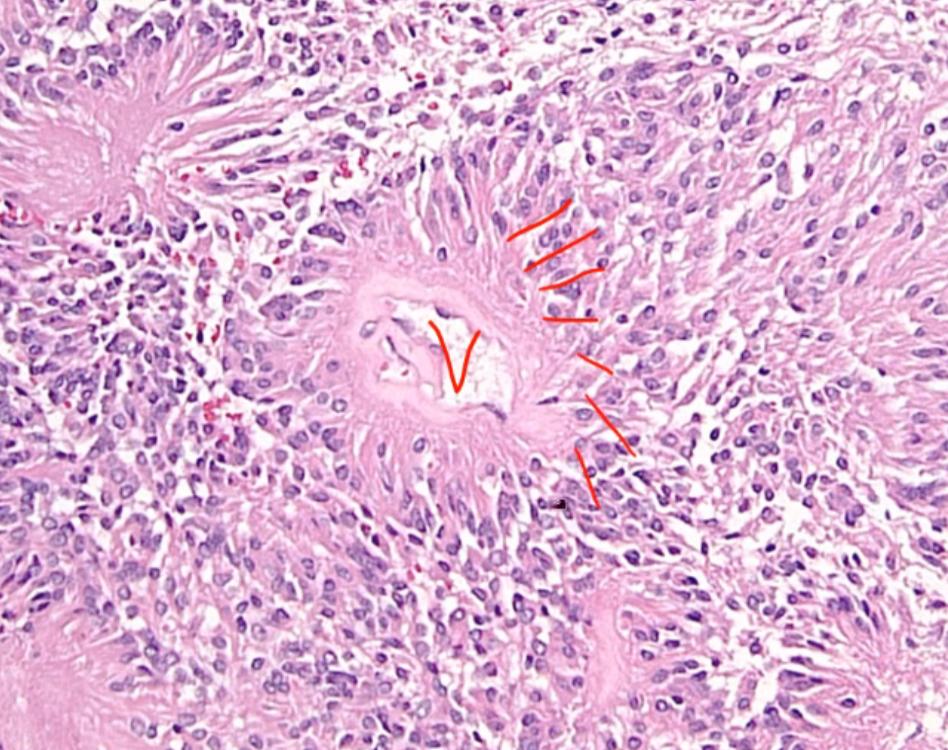

Schwannoma

locate more peripherally

S100 marker of schwann cells